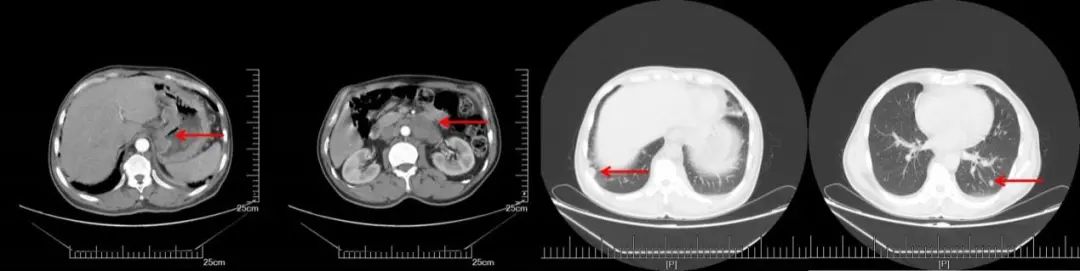

A:CT增强(2018.11.07): 腹膜后多发淋巴结转移,部分较前增大。双侧锁骨上淋巴结转移,部分较前增大,双肺多发结节,转移可能;B:CT增强(2019.05.16):腹膜后淋巴结较前缩小,双肺转移较前增多增大;C:CT增强(2019.10.25):腹膜后淋巴结稳定,双肺转移较前增多增大;D:CT增强(2020.05.27):双肺转移瘤及腹腔淋巴结总体稳定。